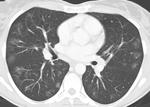

В ходе обследования обращало на себя внимание увеличение уровня лейкоцитов (20*109 /л) и эозинофилов  (40 %),  лимфопения (7%), СОЭ – 70 мм/ч при нормальном уровне гемоглобина,  повышение уровня IgЕ до 461 МЕ/мл. СРБ - резко положительный, гипергаммаглобулинемия. А анализах мочи патологических изменений не обнаружено.  Ан. мокроты: эритроциты 60-80 в п-зр,  эозинофилы 20-30 в п/зр, альвеолярные макрофаги – большое кол. МБТ, грибы не найдены. Спирография - выраженные нарушения вентиляционной способности легких смешанного типа. Бронхоскопия. 2- сторонний поверхностный эндобронхит (1 ст). Микрофлора не выделена.  В анализе кала без особенностей, гельминты и яйца глистов не обнаружены.  Анализы крови на p-ANCA, биопсия легочной не сделаны по объективным причинам.  Следует отметить, что только у 48–66 % пациентов в периферической крови определяются p-ANCA. Данные КТ при поступлении (см. рисунки). Наличие аллергии , аллергического ринита, бронхиальной астмы, гиперэозинофилии, лёгочных инфильтратов,  выпота в плевральной  полости, перикарде, лейкоцитоза, повышения СОЭ, повышения уровня СРБ, выраженной слабости, лихорадки позволили высказать предположение о синдроме Черджа-Стросса. Указанные признаки соответствовали второй фазе болезни.

В результате лечения исчезли признаки бронхиальной обструкции, уменьшилась эозинофилия периферической крови до 6 %, СОЭ снизилась до 22 мм/час. По данным КТ органов грудной клетки (будут представлены позже) отмечена  выраженная положительная динамика в лёгких.  Выпот в плевральной полости и перикарде не определялся. Увеличение лимфатических узлов средостения сохраняется. В удовлетворительном состоянии больной выписан под наблюдение ревматолога. Приведённое наблюдение с оценкой течения заболевания указывает на типичное течение синдрома Черджа–Стросса, несмотря на отсутствие морфологического подтверждения. Специалистов сайта по КТ очень прошу дать характеристику выявленных изменений в ОГК. Пока все. Nikolas.

Достаточно неспецифичная картина: билатеральное (больше справа) снижение пневматизации,  от зон "матового стекла" до консолидации с "воздушной бронхограммой", утолщение стенок бронхов, утолщение парасептального интерстиция, гидроторакс, немного жидкость в перикарде видна. Об узелковых изменениям по картинкам судить невозможно. Справа паракостально не то фиброз плевры, не то осумкованный гидроторакс - сказать трудно. Увеличения лимфоузлов средостения не разглядела, может, не в срезе или проблемно на преимущественно легочном окне увидеть.

5. Мигрирующий характер инфильтратов по КТ. Тут надо остановится поподробнее. Мигрирующий характера может быть как и при СЧС так и при ХЭП. Важно именно характер инфилтрации. В случае с СЧС инфильтрация в основном имеет дольковое распределение  - что это такое: посмотрите с ссылки что я выше привел картинки в конце статью - то есть выглядит как небольшие очаговоподобные инфильтраты. Также для СЧС характерна очаговость. В случае же ХЭП в начальные периоды преобладают именно консолидации, без четких контуров с вовлечением различных сегментов (хаотично). Мигрирующий характер консолидации также встречается часто.

То есть основным диф.диагностическим критерием по КТ между СЧС и ХЭП будет именно ХАРАКТЕР ИНФИЛЬТРАЦИИ. В нашем случае - характер больше в пользу ХЭП (она более массивная , явных признаков очаговости процесса не видно)

Сорри , написал пост - потом еще раз все пересмотрел - больше в пользу СЧС. Все решил гидроторакс и гидроперикард :)) А вот критерий характера инфильтрации к сожилению не такой четкий. Но при СЧС все таки очаговоподобность больше. Если бы не было системности поражения - то ставил бы все таки ХЭП.

Как мне сообщили сегодня, прибавился признак 5. Мигрирующий характер инфильтратов.

Показываю "признак 5. Мигрирующий характер инфильтратов" (# 42). Пациенту проводится лечение кортикостероидами. Состояние удовлетворительное. При поступлении материалов исследования буду  Вас информировать. С уважением ко всем участникам обсуждения клинического наблюдения, Nikolas